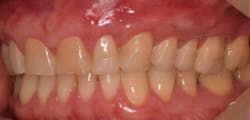

This new biological approach involving blood derivatives A-PRF and I-PRF combined with precision minimally invasive surgery for root coverage demonstrates faster healing without the need of a donor site. The morbidity of GDT is decreased and patient case acceptance is higher compared with traditional grafts. Before-and-after pictures are shown below (figures 15–22).